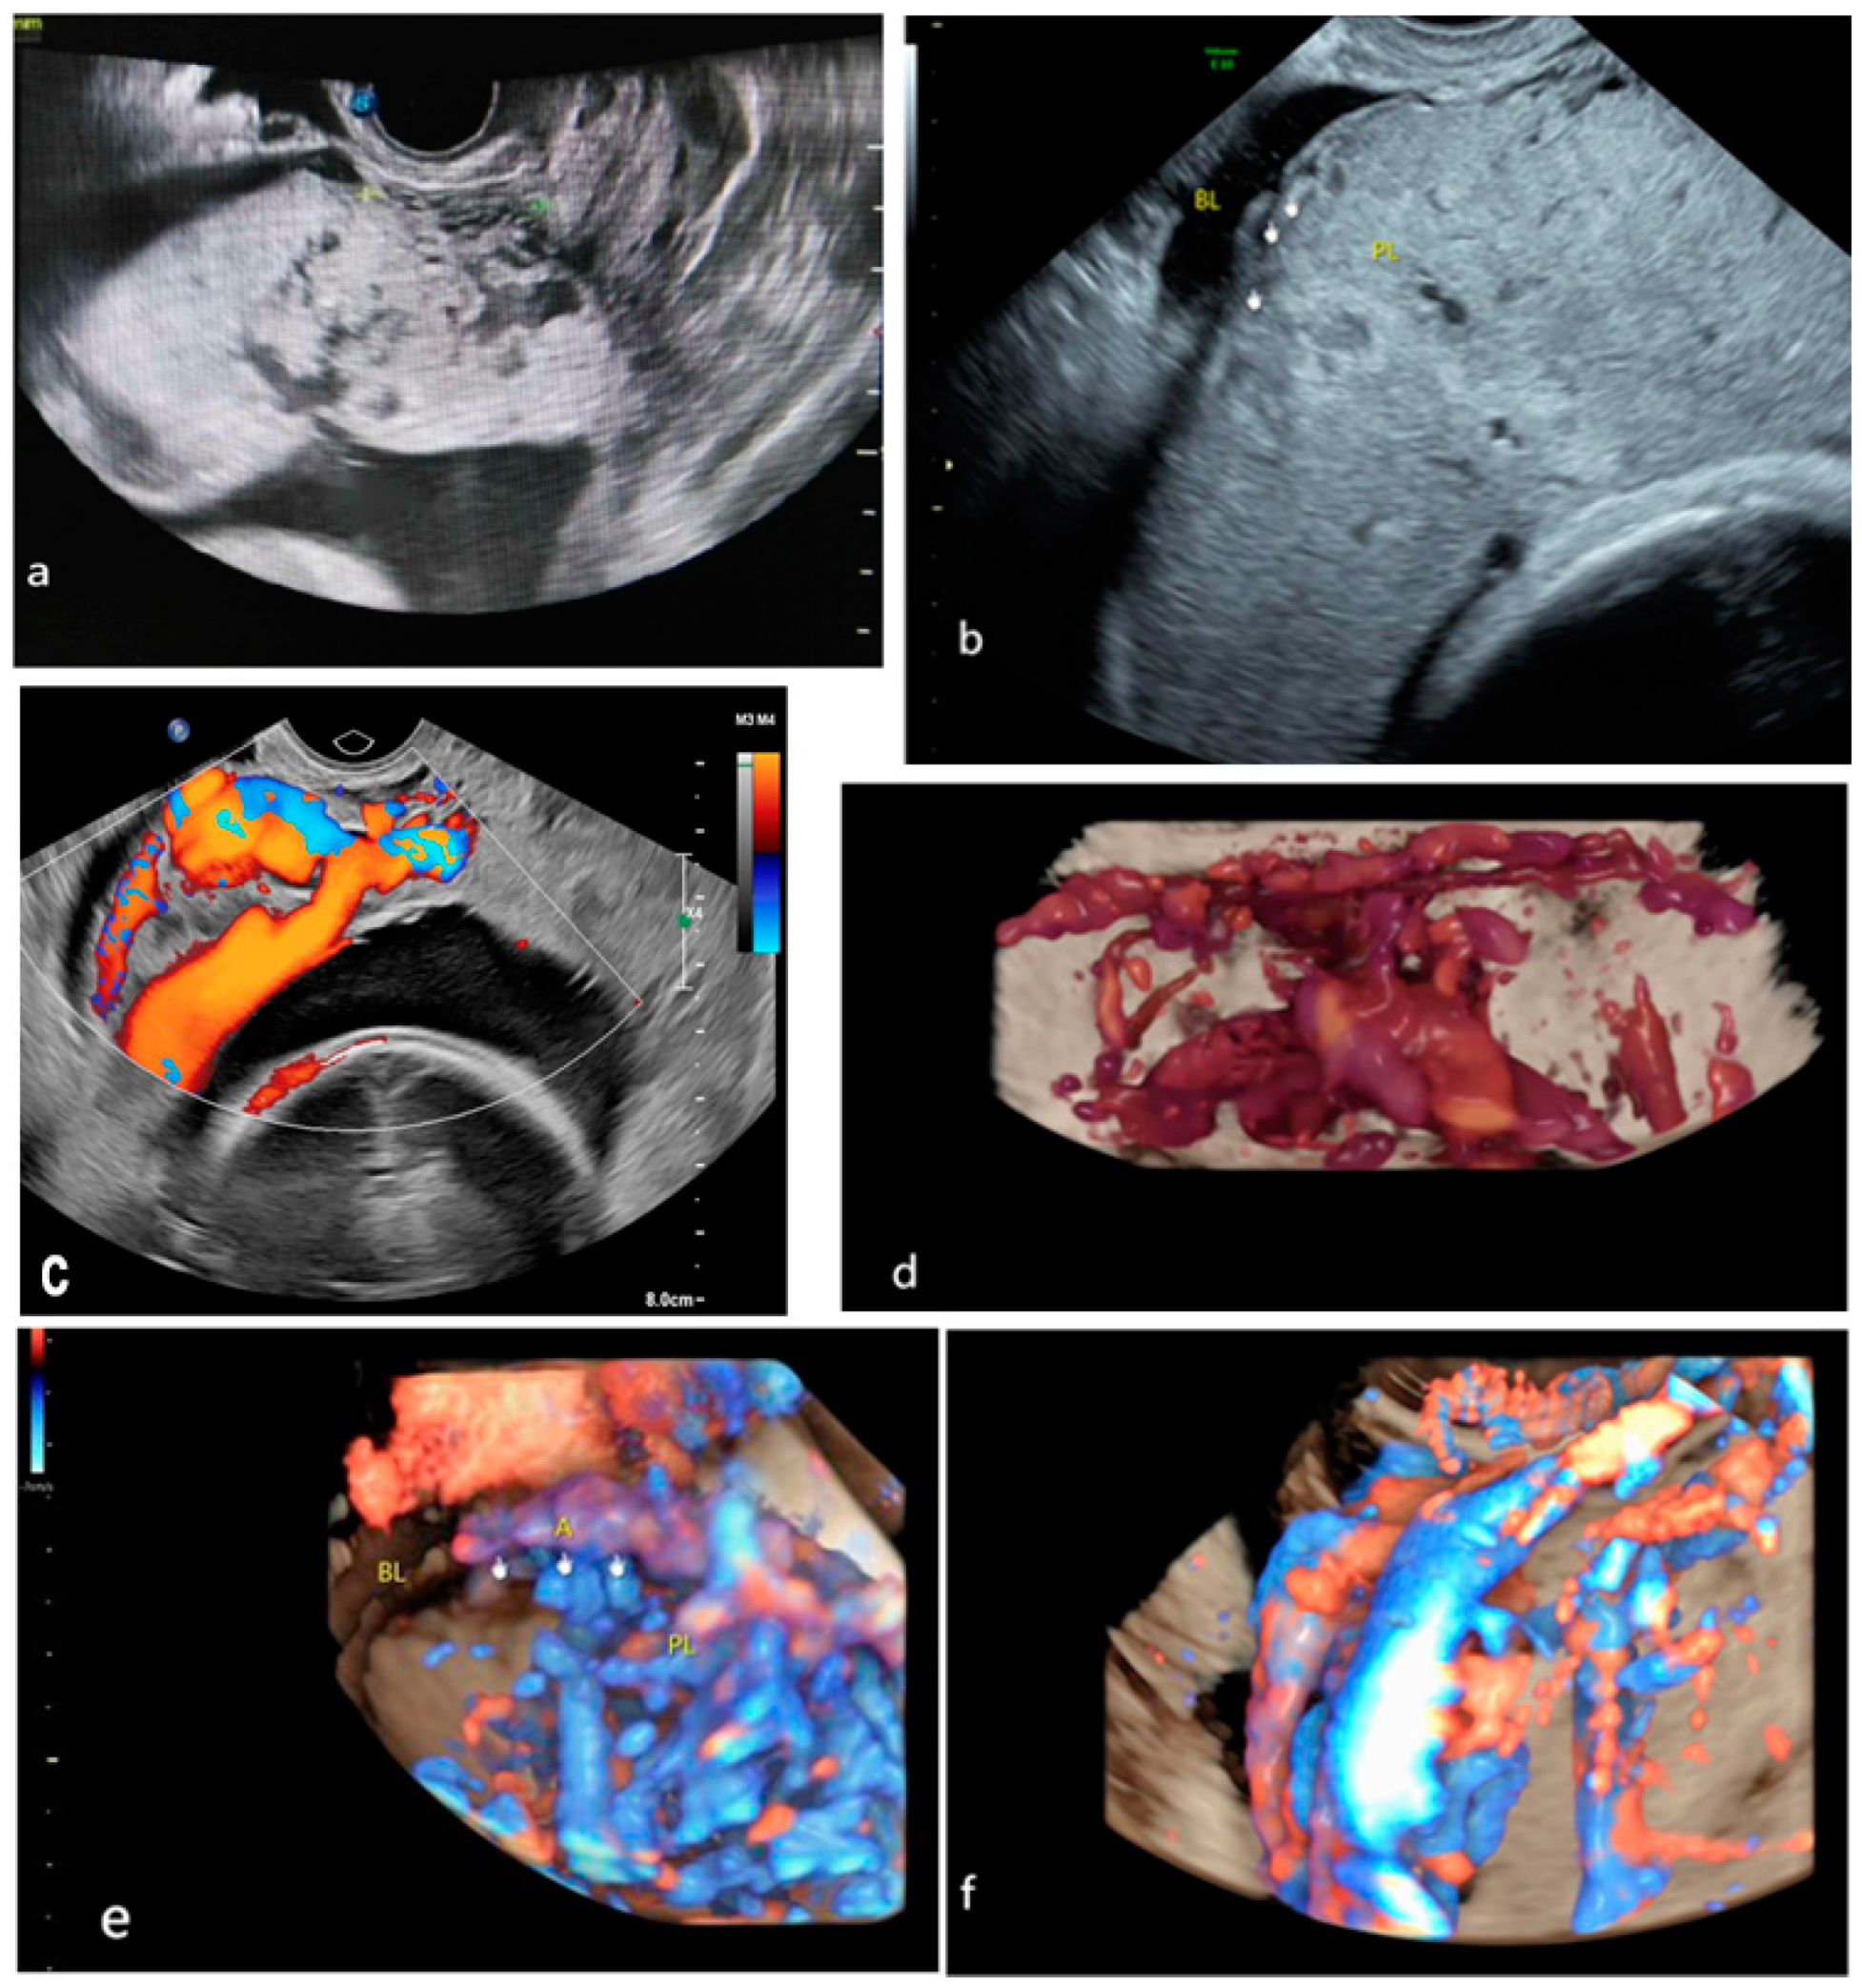

Figure 2.

Common traditional ultrasound signs: (a) placental lacunae; (b) myometrial thinning; (c,d) bladder wall interruption; (e,f) bridging vessels. BL, bladder. A, artery. PL, placenta.